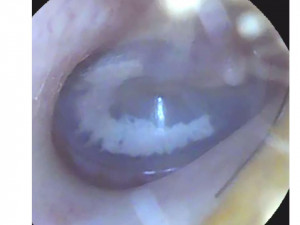

В процессе сурдопедагогического обследования выявлены минимальные расстройства слуховых функций. Игровая тональная аудиометрия: правое ухо – 17,5 дБ, левое ухо – 20 дБ.

Отоскопия приложена.

Скажите, пожалуйста, является ли представленная отоскопия слуховых проходов и барабанной перепонки нормативной?

Здравствуйте. По фото барабанные перепонки выглядят неостро изменёнными: признаков гноя, перфорации или выраженного воспаления не видно, но отмечается втянутость и изменение цвета, что может соответствовать хронической дисфункции евстахиевой трубы или последствиям перенесённых серозных отитов. Это не является строго нормой.